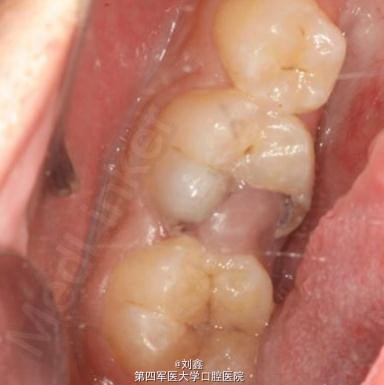

男,16岁,46因牙龈息肉就诊。

46牙牙龈息肉

局麻下牙龈息肉切除及开髓去腐,后牙根管治疗后纤维桩+树脂充填